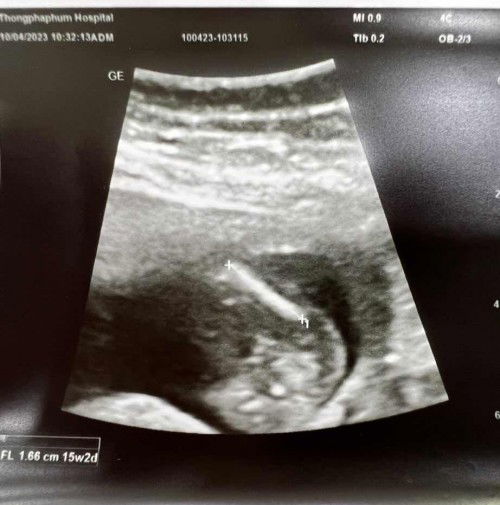

ภาพอัลตราซาวด์

สอบถามแม่ๆค่ะ ว่าน้องเป็นผู้หญิง รึ ผู้ชาย เพราะป้าหมอแจ้งว่า ในภาพอัลตราซาวด์มองไม่ชัดและยังไม่แน่ใจ #ขอคำแนะนำหน่อยค่ะ #ท้องแรกคะ